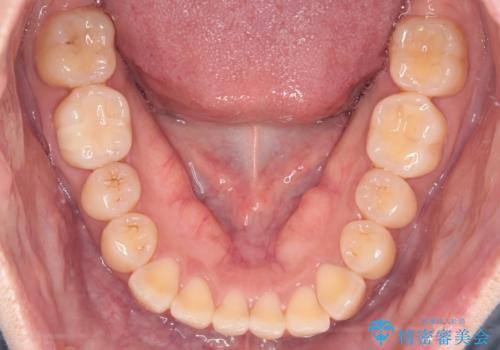

- 上の前歯の捻れを主訴に来院されました。

前歯の捻れとがたつきを改善するために、IPR(歯と歯の間を削る処置)と歯列拡大をすることで歯並びを整えていく治療計画を立てました。

かみ合わせを整えるためにゴム掛けも行いながら、治療していきました。

患者様にマウスピースの使用とゴム掛けを頑張っていただいたおかげでリファイメント(マウスピースの再発注)も1回で終了することができました。